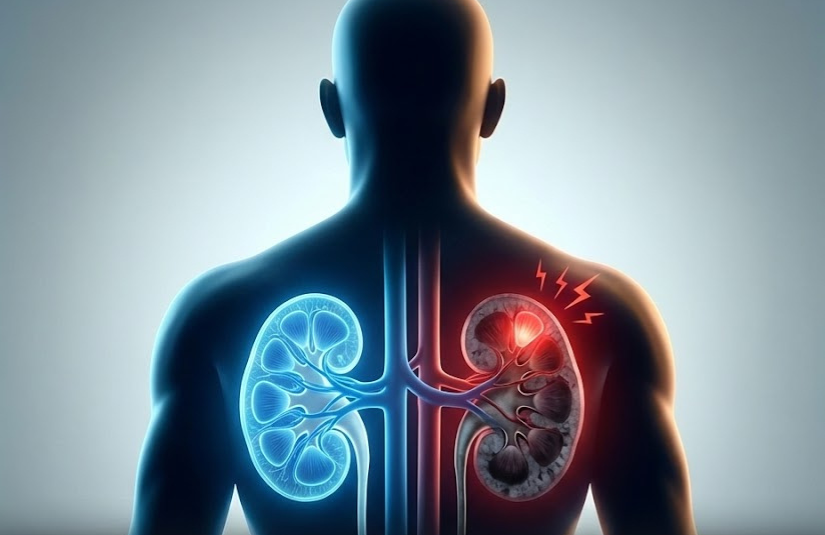

Захворювання нирок — це прихований, але дуже серйозний стан, який може завдати шкоди всьому організму. Нирки — життєво важливі органи, що невпинно фільтрують кров, виводять токсини та регулюють артеріальний тиск. Раннє розпізнавання тривожних сигналів має вирішальне значення, адже своєчасне звернення до лікаря може запобігти ускладненням.

Ниркова недостатність може бути спричинена високим артеріальним тиском, діабетом, інфекціями або аутоімунними захворюваннями. Не ігноруйте ці 10 ознак, щоб захистити своє здоров’я.

4. Незрозумілий біль у спині